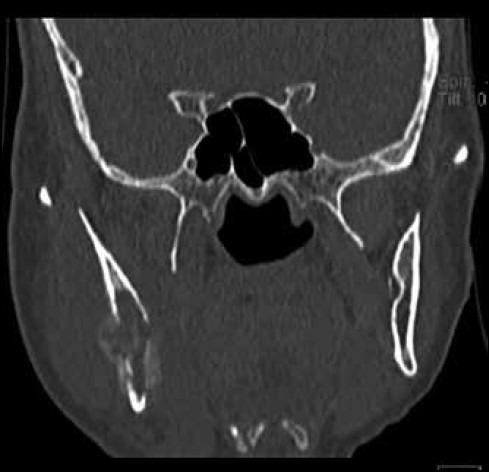

Mandibular metastasis from a pulmonary squamous cell carcinoma.

Metastatic tumors to the jaws and oral tissues are rarely encountered, accounting for less than 1% of all malignant tumors affecting the mouth. Although, metastasis to the mandible from a pulmonary carcinoma is extremely rare, when it does occur it mimics more common pathoses such as odontogenic cysts, osteomyelitis, space infections making its diagnosis even more challenging. Metastasis should be taken into account especially in patients with chronic history of smoking and sudden onset of paresthesia. The rarity of such cases has also resulted in there being no definitive consensus on managing them.

转移至颌骨和口腔组织的肿瘤很少见,占所有口腔恶性肿瘤的比例不到1%。虽然肺癌转移至下颌骨极为罕见,但一旦发生,它会模仿更常见的病症,如牙源性囊肿、骨髓炎、间隙感染,这使得其诊断更具挑战性。特别是对于有长期吸烟史且突然出现感觉异常的患者,应考虑转移的可能性。此类病例的罕见性也导致在治疗方法上没有明确的共识。